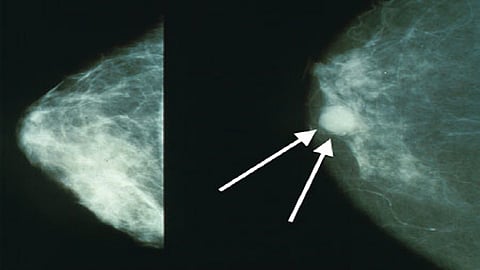

मुंबई : मुंबईतील परळ येथील टाटा रुग्णालयाने केलेल्या संशोधनानूसार, आता केवळ 3 महिन्यांच्या औषधोपचारांनीच स्तनाचा कर्करोग बरा होऊ शकणार आहे. शिवाय यामुळे औषधोपचारांना लागणारा खर्चही कमी होणार आहे. रुग्णालयाने 11 हजार रुग्णांवर केलेल्या चाचणीतून हा निष्कर्ष काढला आहे. टाटा मेमोरियल रुग्णालयाचे संचालक डॉ. राजेंद्र बडवे, एसीटीआरईसीचे संचालक डॉ. सुदीप गुप्ता आणि टाटा रुग्णालयातील डाॅक्टर गेल्या 15 वर्षांपासून यावर संशोधन करत होते.

या औषधाच्या मूळ ब्रँडची किंमत 8 ते 10 लाख रुपये असुन ते सर्वसामान्यांना न परवडणारे आहे. शिवाय वर्षभर औषध घेतल्याने हृदयावरही त्याचे विपरित परिणाम होते. या कारणांमुळे गेल्या पंधरा वर्षांपासून उपचाराचा कालावधी कमी करण्यावर संशोधन सुरु होते. अखेर टाटा मेमोरियल रुग्णालयाच्या डॉ. सुदीप गुप्ता यांच्या मार्गदर्शनाखाली सुरू असलेल्या संशोधनाला यश आल्याचे डाॅ. बडवे म्हणाले. भारतीय महिलांमध्ये ' एचइआर 2' या प्रकारातील स्तनाचा कर्करोग सर्रास आढळून येतो. अशा महिलांंना या दोन्ही गोष्टींमुळे मोठा दिलासा मिळणार असल्याचेही ते म्हणाले.

आम्ही स्तनाच्या कर्करोगाबाबत अभ्यास करत होतो. त्याची उपचार पद्धती कशी कमी करता येईल यावर संशोधन सुरु होते. मात्र, आता नव्याने समोर आलेल्या उपचार पद्धतीमुळे एका वर्षांचा कालावधी थेट 3 महिन्यांवर आला आहे. एचइआर 2 हा स्तनाचा कर्करोग देशातील 25 टक्के लोकांमध्ये आढळतो.